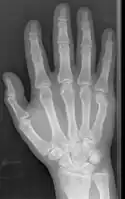

Boxer fracture

Boxer fracture of the 4th and 5th knuckles